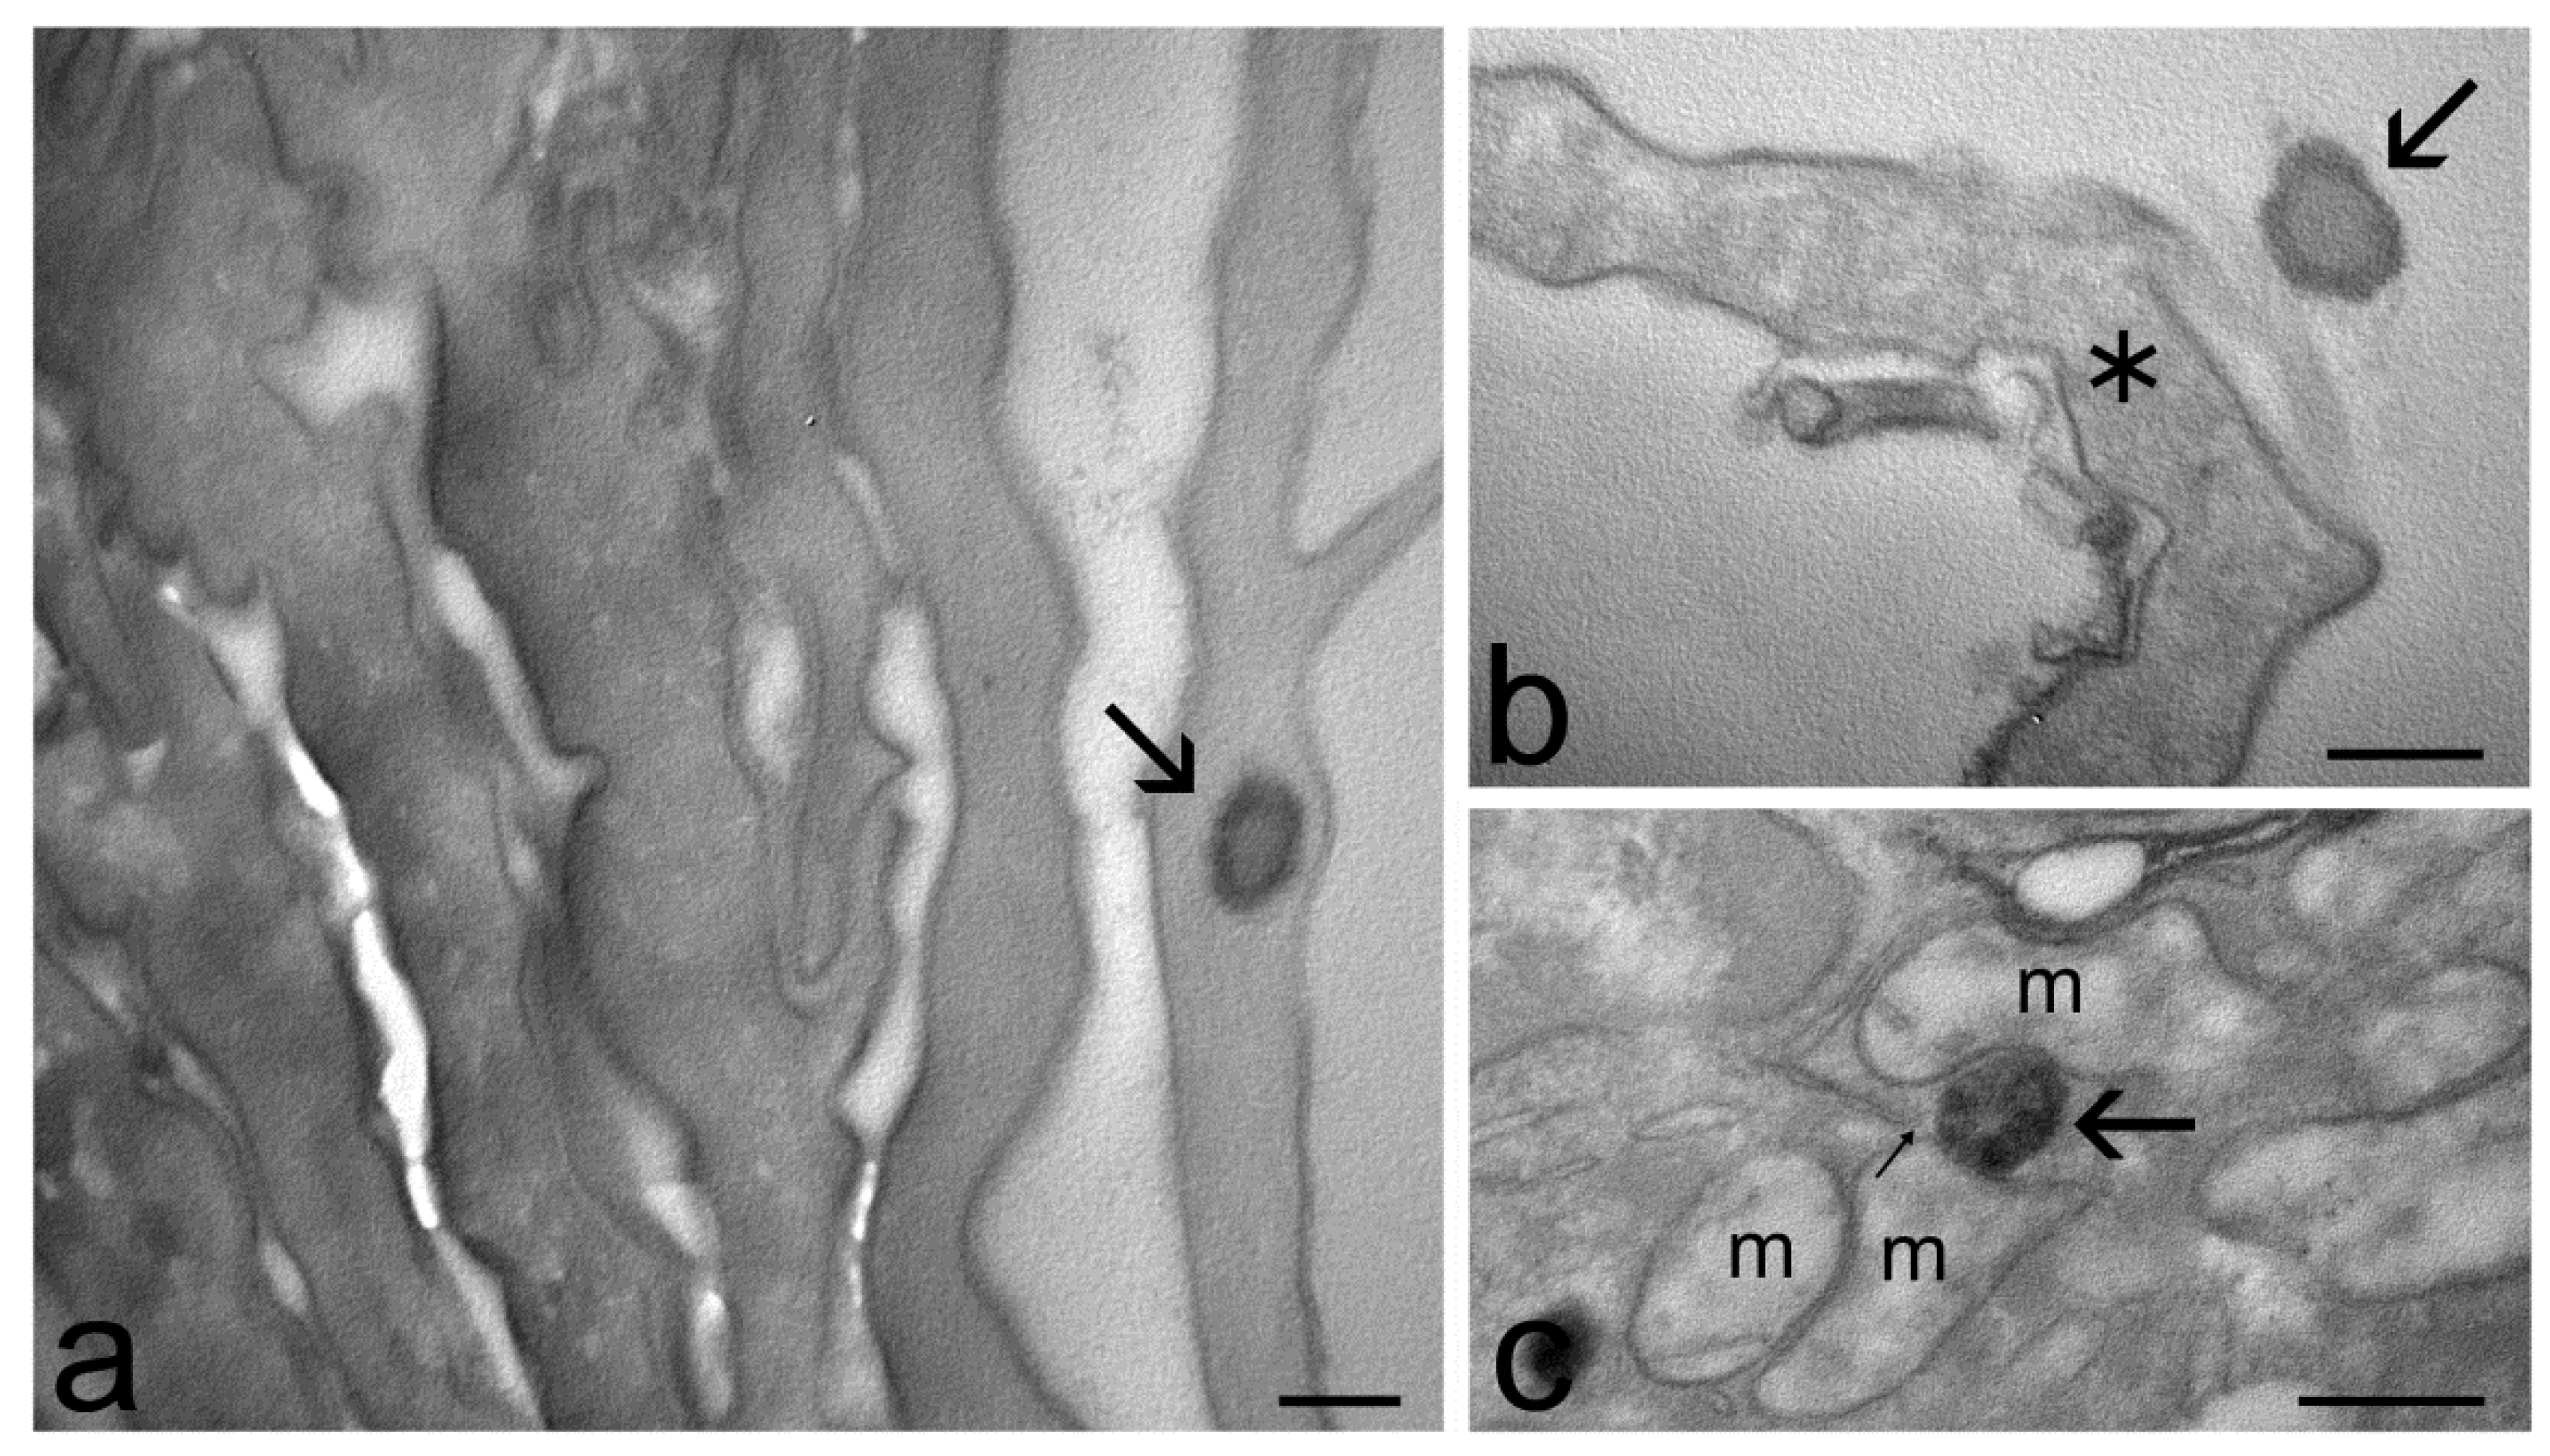

2.4. Transmission Electron Microscopy Study of Skin Penetration

4.4. Cryo-Transmission Electron Microscopy

4.7. Transmission Electron Microscopy Study of Skin Penetration